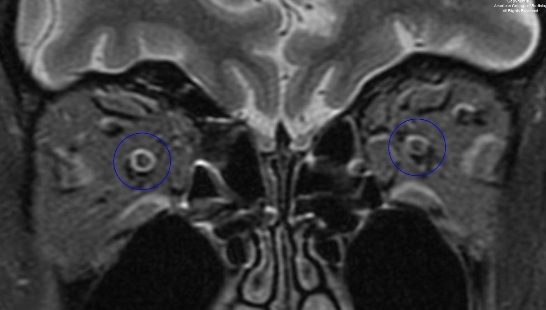

图 6 为冠状 STIR 序列示视神经未见异常(圈)

7.jpg

图 7 为冠状 T1 强化伴压脂序列示双侧视神经对称,未见异常强化(圈)